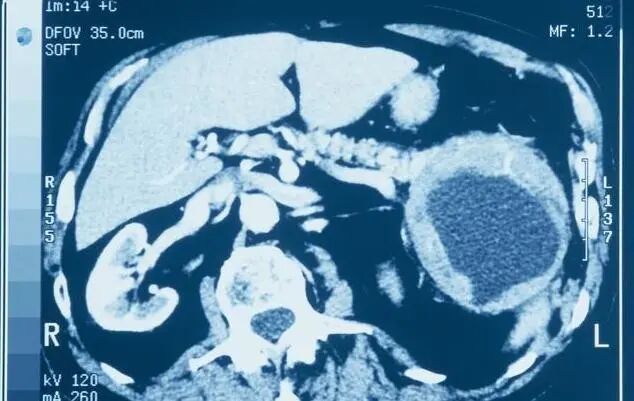

综上所述,胰腺癌更青睐于有慢性胰腺炎的人、初发的糖尿病患者、长期吸烟饮酒及生活不规律的人、有家族史的人,而且男性多于女性,老年人更容易患病。因此建议这些高危人群要重视预防,养成良好的生活习惯,并要定期体检,抽血化验、做B超或CT检查,力求做到早发现、早诊断、早治疗。

对于这类人群的筛查,推荐检查手段依次为EUS、 MRI/MRCP、CT、腹部超声、ERCP,必要时可结合胰液分析或者细针穿刺检查。研究发现,绝大多数高危人群胰腺病变表现为囊性病变。目前对于无症状的囊性肿瘤患者建议首选MRI作为随访手段,对于直径小于3cm无症状、无胰管改变、无实性成分的囊性肿瘤患者可1年后复查,若仍无变化则以后可每2年随访1次,若随访5年后该囊性肿瘤仍无变化可终止随访。